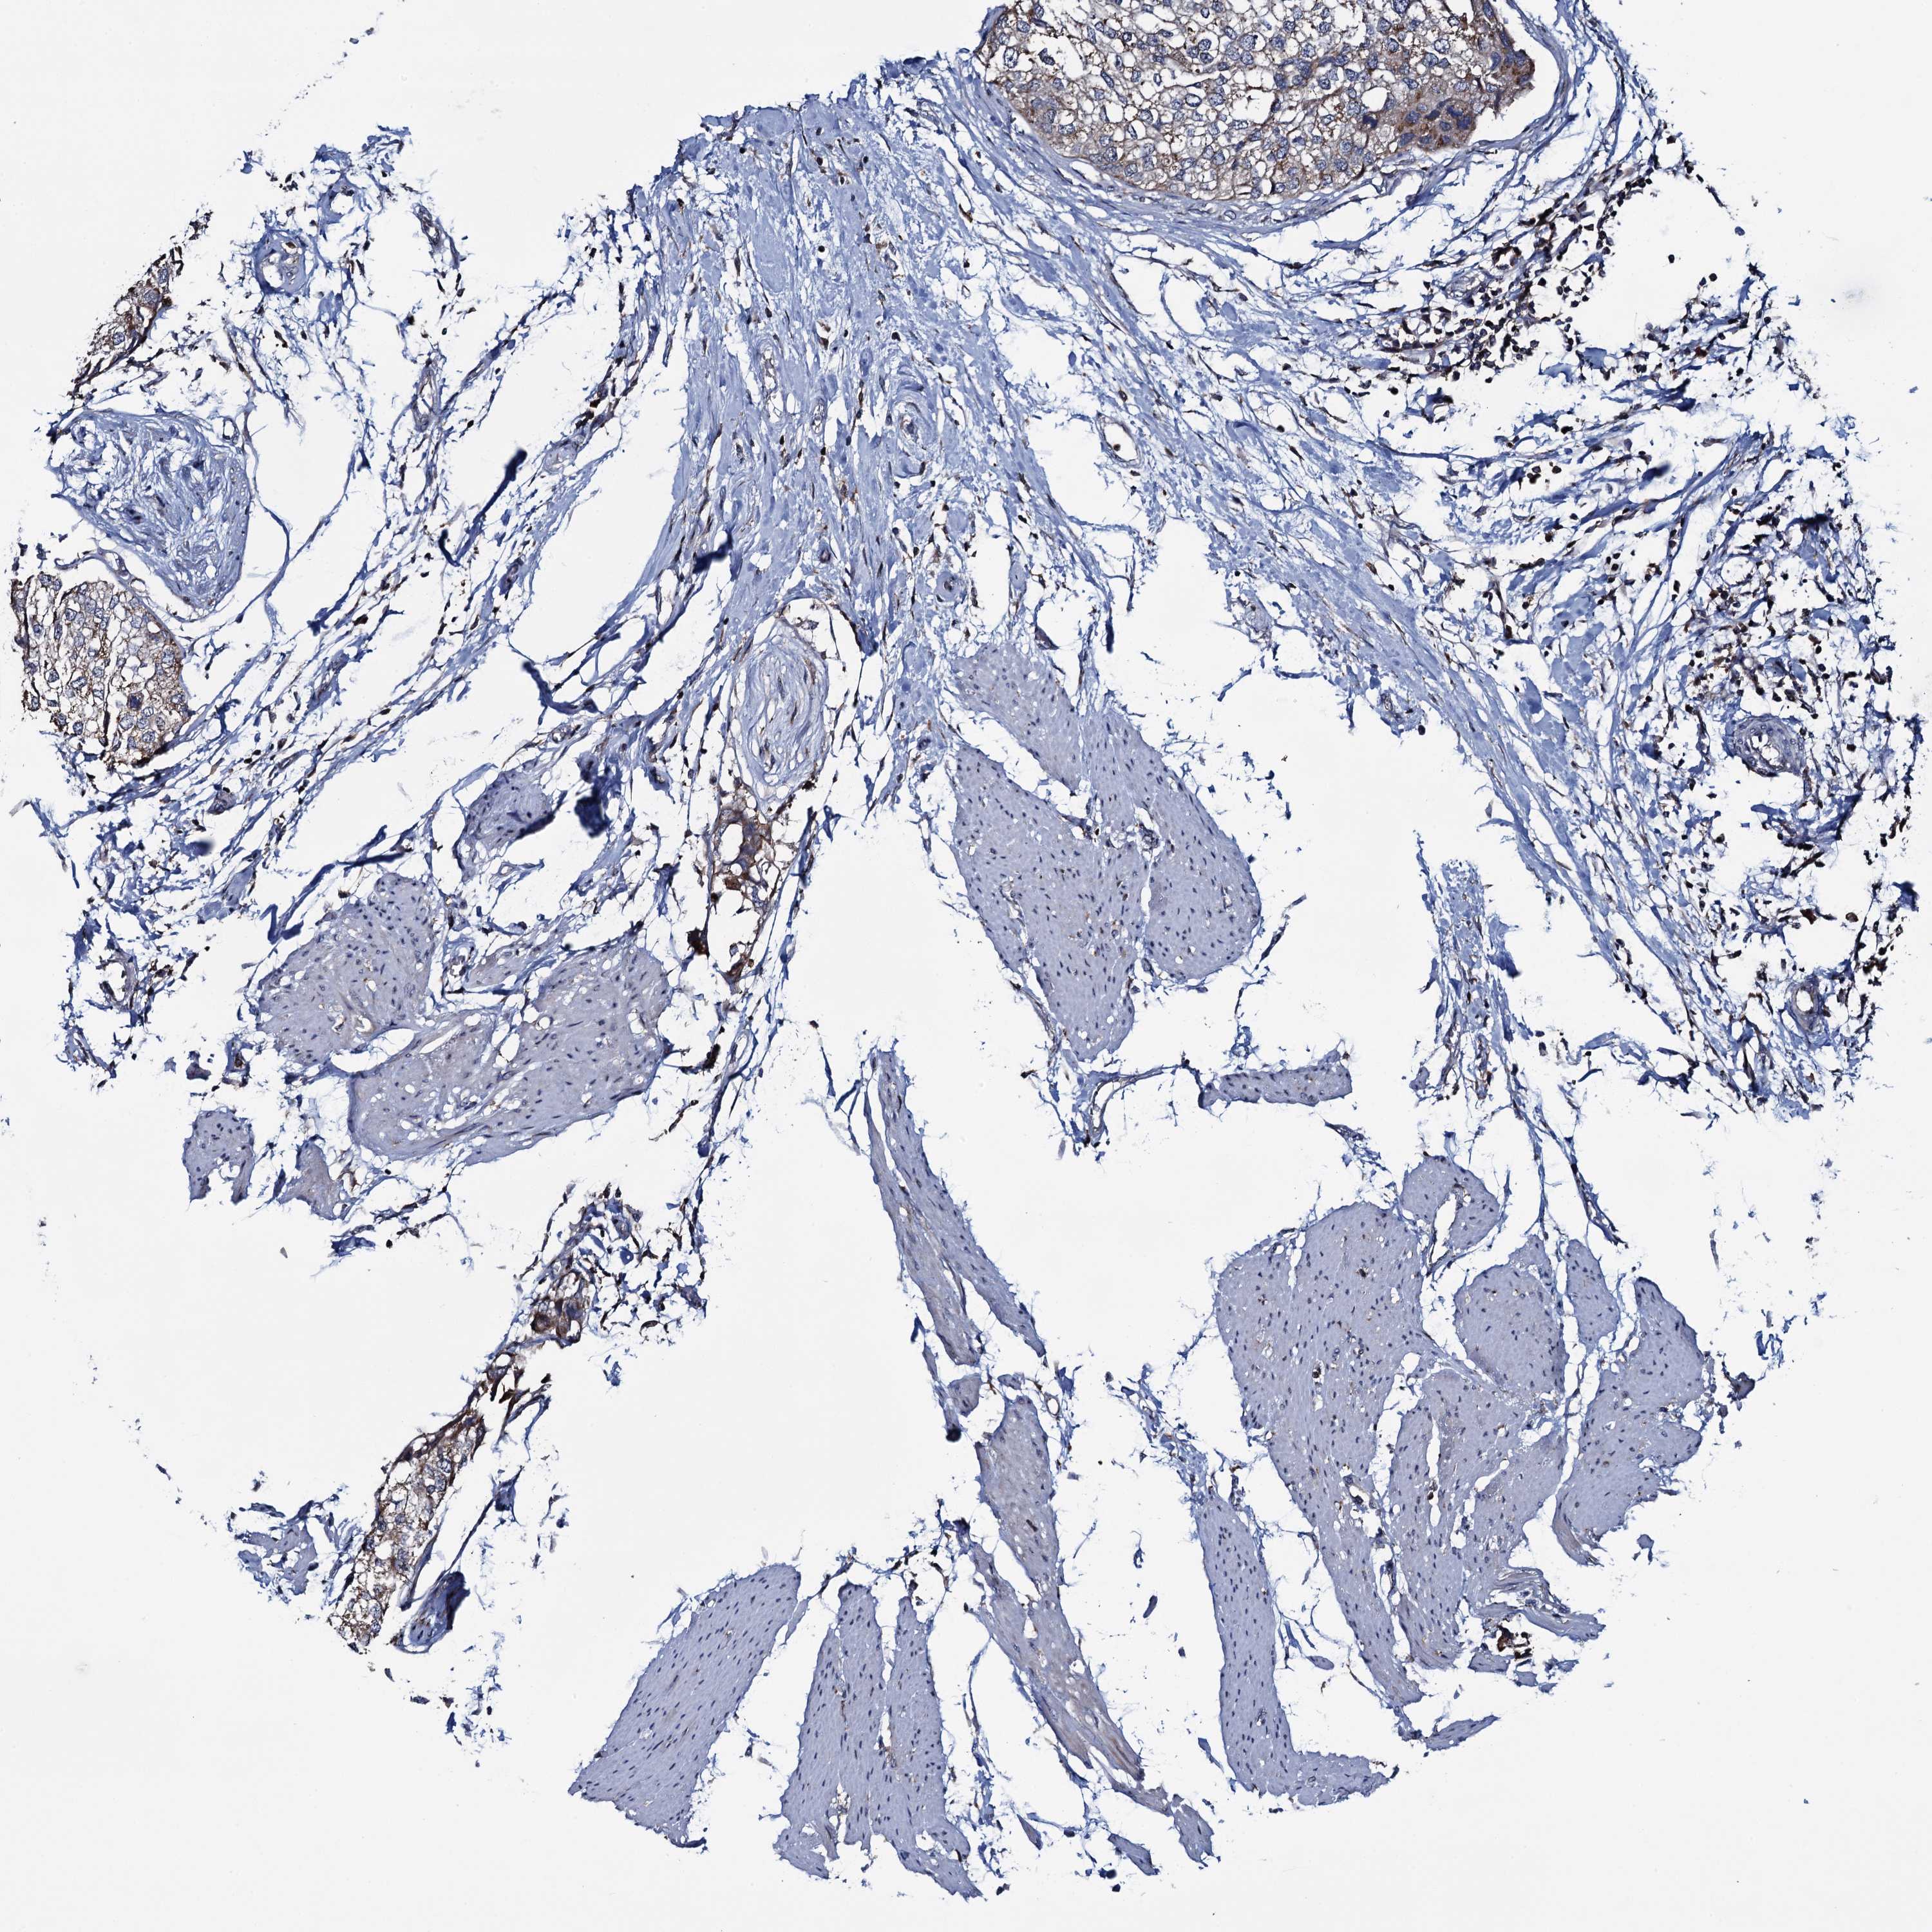

UROTHELIAL CANCER - Protein expressioni

A mouse-over function shows sample information and annotation data. Click on an image to view it in a full screen mode. Samples can be filtered based on level of antibody staining by selecting one or several of the following categories: high, medium, low and not detected. The assay and annotation is described here.

Antibody stainingi

Antibody staining in the annotated cell types in the current human tissue is reported as not detected, low, medium, or high, based on conventional immunohistochemistry profiling in selected tissues. This score is based on the combination of the staining intensity and fraction of stained cells.

Each image is clickable and will lead to virtual microscopy that enables deeper exploration of all samples and also displays staining intensity scores, fraction scores and subcellular localization as well as patient and tissue information for each sample.

Antibody HPA040598

Antibody HPA040958

Urothelial carcinoma, Low grade